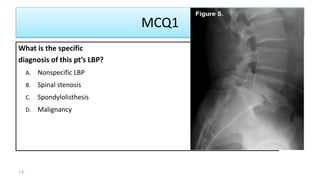

MCQ1

What is the specific

diagnosis of this pt’s LBP?

A. Nonspecific LBP

B. Spinal stenosis

C. Spondylolisthesis

D. Malignancy